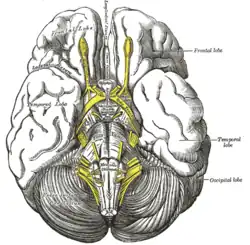

Base of brain (anterior perforated substance labeled at center.) | |

The anterior perforated substance is a part of the brain. It is bilateral. It is irregular and quadrilateral. It lies in front of the optic tract and behind the olfactory trigone.

The anterior cerebral artery arises just below the anterior perforated substance.[3] The middle cerebral artery passes through its lateral two thirds.[4]

Blood supply

The anterior perforated substance is supplied by lenticulostriate arteries, which branch from the middle cerebral artery.[4] It is also supplied by anterior choroidal artery.[4] Small branches from these create holes, which give the anterior perforated substance its name.[1]